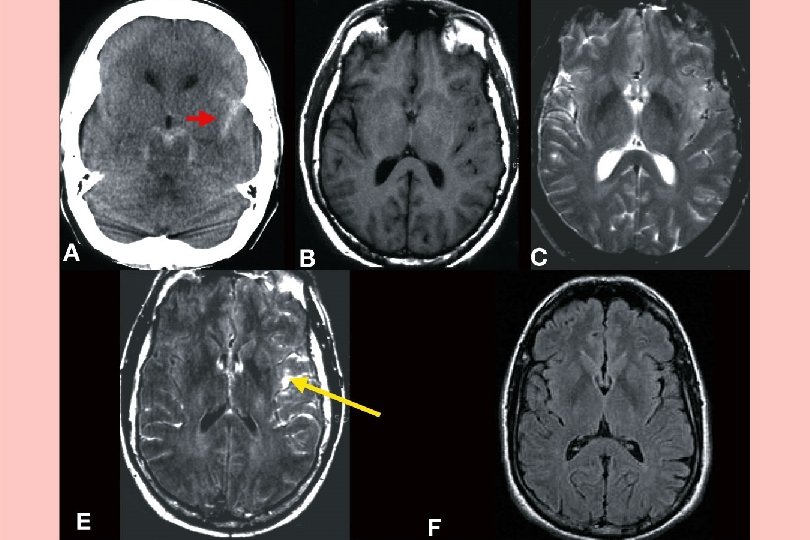

Intra cranial pain

Where does the pain come from? Intra – cranial (dural pain fibres) n Tension – raised intracranial pressure n Compression – tumour n Inflammation - migraine, meningitis, blood

Sub Arachnoid - thunderclap headache

Reversible vasoconstriction syndrome Vasoconstrictor drugs, SSRIs, Cannabis

Thrombophilia

Meningitis

Malignant hypertension

Space occupying lesions Stretch, compression, blockage n Benign – cysts, A-V malformations n Malignant – primary secondary